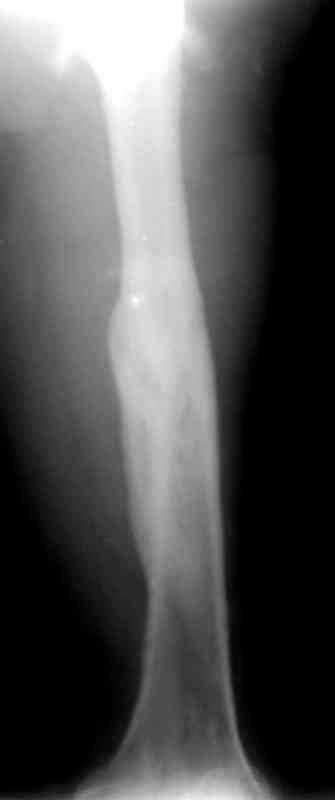

месяцев дистракции укорочение левого бедра удалось полностью устранить. 22.02.00, т.е. через 2 месяца после повторного остеосинтеза, больному произведено дистальное блокирование штифта двумя винтами и демонтирован аппарат Илизарова. В течение 2 недель после операции больной ходил с помощью костылей, потом 2 недели с тростью. Опороспособность и функция оперированной конечности полностью восстановились через 4 недели после операции.

Фиксаторы удалены через 12 месяцев после операции, выполненной по поводу замедленной консолидации перелома бедра с его укорочением.

Спасибо! Истинно мастерская работа. Представляю как счастлив пациент исходом этой истории.

На финальных снимках видно - сращение прям таки железное. Если Вы не устали отвечать, осмелюсь задать еще вопрос - что-то принимал пациент в целях ускорения сроста (кальций, режим питания). Интересны также вопросы восстановления функций конечности - в какой период были рекомендованы группы упражнений для восстановления основных групп мышц?